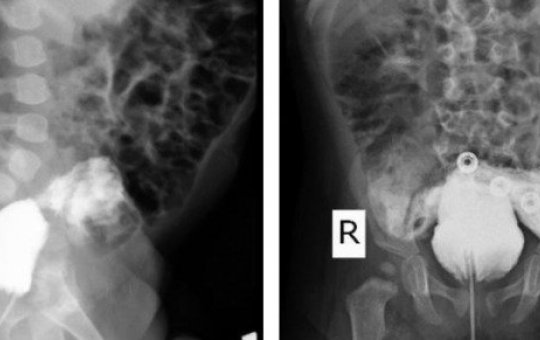

Bebê no Irã surpreende ao nascer sem pênis e urinar pelo ânus

Caso ganhou um relato científico na revista médica Radiology Case Reports